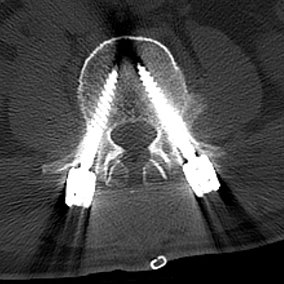

陈勇主任团队顺利为患者置入椎弓根螺钉。术后患者腰腿痛症状较术前明显缓解,肢体活动无障碍,术后3天即在脊柱支具外固定的辅助下下地行走,术后第7天患者恢复情况良好,顺利出院。

▲术中椎弓根螺钉精准置入

术后复查X线、CT

椎弓根螺钉内固定技术是目前脊柱手术中最常应用的固定技术,但在椎弓根置钉过程中存在损伤神经与血管的风险。提高置钉安全性及成功率一直是脊柱外科医师研究的重要内容。